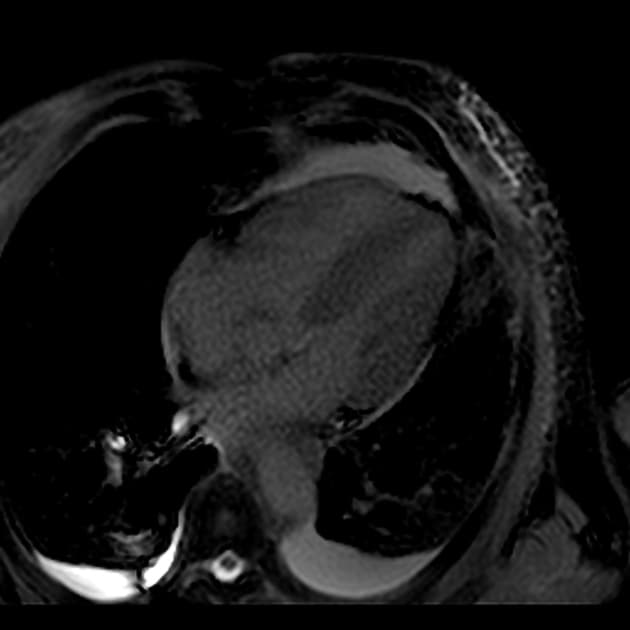

4 chamber PSIR gado

MRI•4 chamber PSIR gado•1 Img

- Bệnh cơ tim phì đại dạng đỉnh thất (apical hypertrophic cardiomyopathy) với tắc nghẽn ở đoạn giữa thất (midventricular obstruction).

- Cả chuỗi hình ảnh LGE và PSIR có tiêm thuốc đối quang (gadolinium) đều cho thấy xơ hóa thành thất dạng ổ (patchy midwall fibrosis), có liên quan đến lớp dưới nội tâm mạc (subendocardial involvement) tại đỉnh thất (apex).

- Necrosis dưới nội tâm mạc ở đỉnh thất (apical subendocardial necrosis) có thể là nguyên nhân gây đau ngực (chest pain).

- Không thấy huyết khối (no thrombus).